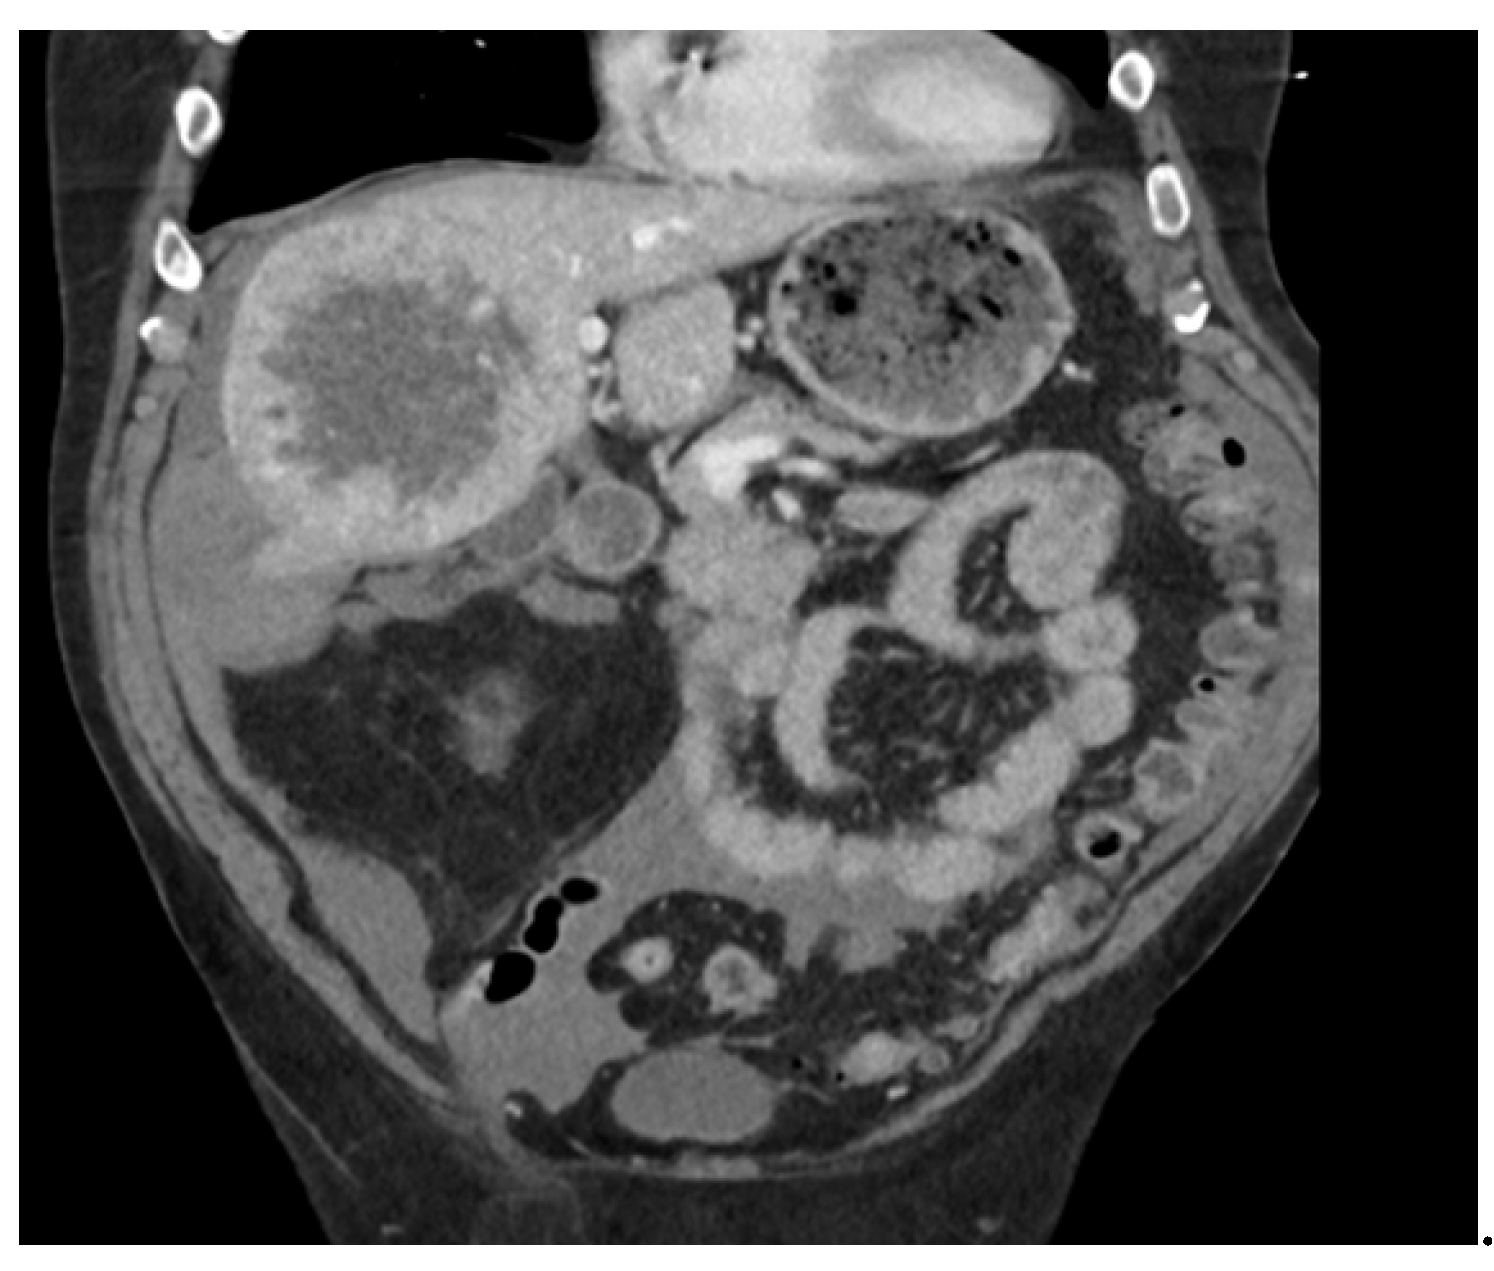

Abdominal Pain Due to Liver Capsule Rupture: A Rare but Fatal Complication of Hepatocellular Carcinoma

2. Case